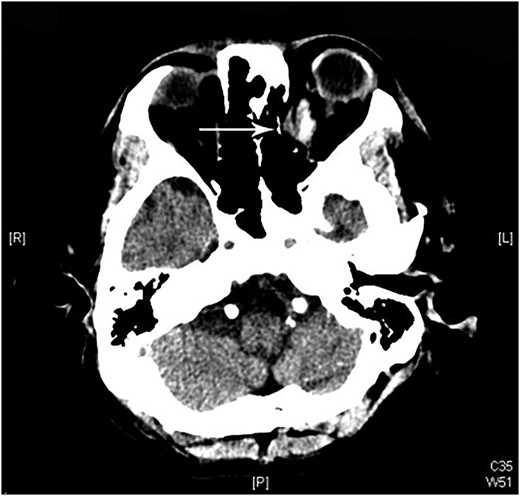

A 60-year-old man was admitted to our medical ward due to aspiration pneumonia. He had a medical history of diabetes mellitus, end-stage renal disease; a tuberculosis bacilli-related thoracic spine infection with paraplegia, and a previous coronary artery bypass graft. During his third day at the hospital, he obtained a ballpoint pen and inserted it into his left eye. On physical examination, the patient appeared to be alert with normal vital signs. The ballpoint pen protruded from his left upper eyelid; it was firmly lodged in his left medial orbit between the globe and nose, causing left eye proptosis (Fig. 1). Neurologic examinations revealed that the patient was neurologically intact except for complete left ophthalmoplegia. Brain CT scanning revealed a tubular foreign body that was located in the anteroposterior plane extending from the orbital apex and directly into the parasellar region (Fig. 2). The metallic portion of the foreign body was entrapped in left optic canal (Fig. 3). There was no evidence of intracranial hemorrhaging or a rupture in the globe (Fig. 4). The patient was treated with high-dose steroids to protect the optic nerve. The plastic ballpoint pen and metallic tip was withdrawn from the orbit smoothly at bedside, and no craniotomy was required. The ballpoint pen had been inserted to an estimated depth of 7 cm through the eyelid and into the orbit. The patient was then transferred to the ICU for close neuro-observation. We initiated intravenous broad-spectrum antimicrobials and vancomycin therapy and continued these medications for three weeks. A psychiatrist was consulted for a complete psychiatric evaluation and suicide prevention. The follow-up CT scan showed no retained foreign bodies or intracranial hemorrhaging (Fig. 5). At the last follow-up examination 2 months after the injury, the patient presented with complete left ophthalmoplegia and blepharoptosis but intact visual function.

The follow-up CT scan shows residual hematoma in the orbital cavity; no retained foreign bodies or intracranial hemorrhaging.